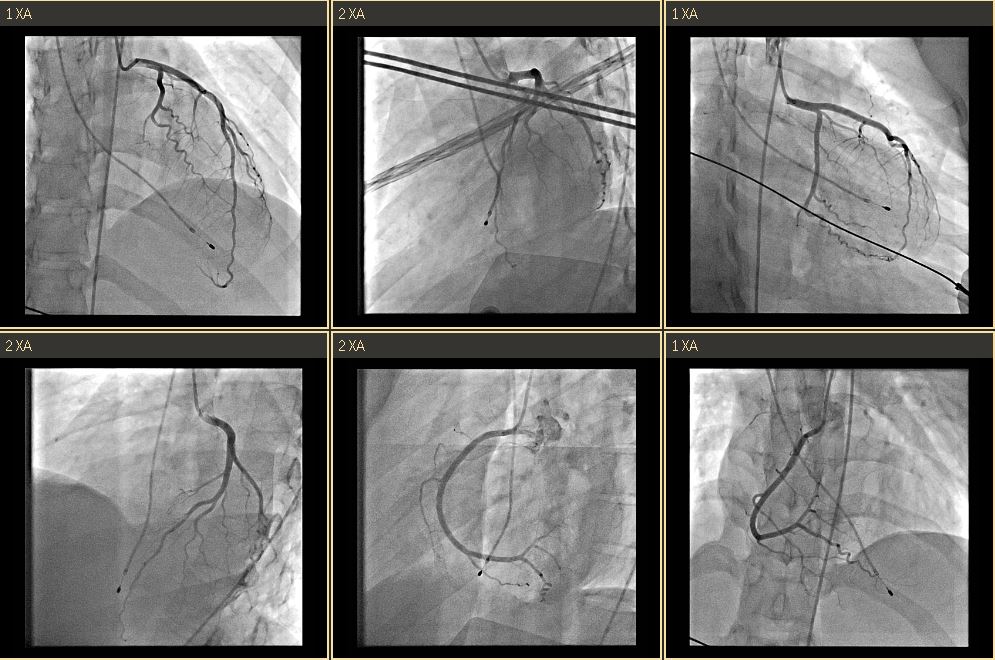

Coronary Angiography:

LM: Patent

LAD: Patent

LCX: Patent

RCA: Patent

**STEP 1: DiagnosticCAG**Puncturedright EIA; placed 6Fr sheath.EngagedLCA with 5Fr JL4 catheter, showing patent LCA, and with 5Fr JR4 for RCA,showing patent RCA.

**STEP 4: Insert ABIOMED Impella CP® Microaxial Flow Catheter for Cardiogenic Shock** Pre-embedded 2 Abbott Perclose ProGlide™ SMC System sutures at right EIA sheath. Inserted Impella sheath; Advanced 0.18 wire to LV with pigtail, and checked Impella CP device for function and primed with saline. Positioned Impella tip in LV using fluoroscopy; removed guidewire and connected to console. Confirmed Impella function; secured access site.

**STEP 5: Removal of Impella on Day 5** Removed Impella after inserting 0.35 J-tip wire to aorta; Achieved hemostasis using ProGlide™ sutures.